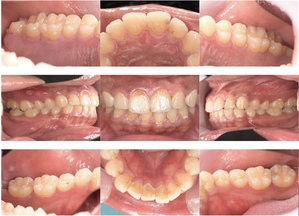

症例3

来院2回目、TBI後

症例

SRP後

初診時、TBI前

基本情報

年齢・性別 27歳・男性

主訴 主訴:左右下の歯ぐきに違和感がある

治療部位:全顎

治療内容 1.歯周基本検査、レントゲン撮影、口腔内写真、歯磨き指導、歯石除去、着色除去

2.SRP(スケーリングルートプレーニング)、再評価

その他

3.親知らずの抜歯

4.カリエス処置:右上1.2.3左上1.2.3右下6左下7CR(レジン充填)、右下7セラミックIn

5.定期検診

治療期間 6ヶ月

治療費 ※歯周基本治療の費用:PMTC以外保険診療3割負担

合計:19,680円

1.初診検査(歯周ポケット検査.レントゲン撮影):3,010円

2.歯磨き指導、歯面の歯石除去:1,410円

3.PMTC(自由診療):5,500円

4.SRP(歯周ポケット内の歯石除去)×4回:約2,000円/回

5.再評価:1,760円

(2023年12月現在)

リスク・副作用 ・最初は歯磨きをすると歯ぐきから出血するが毎日ホームケアを続けることで出血が徐々になくなる

・歯ぐきが腫れている状態が改善されると歯ぐきが引き締まり退縮するため、歯ぐきが下がったように感じることがある

・歯ぐきが引き締まると歯間が開いたように感じることがある

・歯ぐきが引き締まると知覚過敏の症状がでる可能性がある

・一度歯石を除去しても毎日のホームケアを怠ると再度歯石がつく

・治療後も再発を防ぐために定期的なメインテナンスが必要である

治療方針 1.初診検査(レントゲン撮影、口腔内写真、歯周検査、歯磨き指導)

2.歯磨きチェック、歯石除去、PMTC

3.SRP

4.再評価

特記事項 ・歯科医院は今回初めて

・タバコは24歳まで3年ほど吸っていたが健康のためにやめた

・親知らずは右下以外抜歯

・歯ブラシはルシェロP20M、補助用具はフロスを処方

担当者所見 全体的に歯と歯ぐきの境目に歯垢(細菌の塊)が残り、日々のホームケアで落とし切れていなかったことと、歯科医院への定期検診の習慣がなかったことから、全顎的な歯肉炎になってしまったと考えられる。

歯周基本治療とホームケアで歯ぐきの腫れや歯周ポケット、出血率などかなり改善されたが、出血がまだ0%ではない為、引き続き歯ブラシの当て方をお伝えしつつ今後は定期検診で3ヶ月おきに再発しないよう一緒に管理していく。